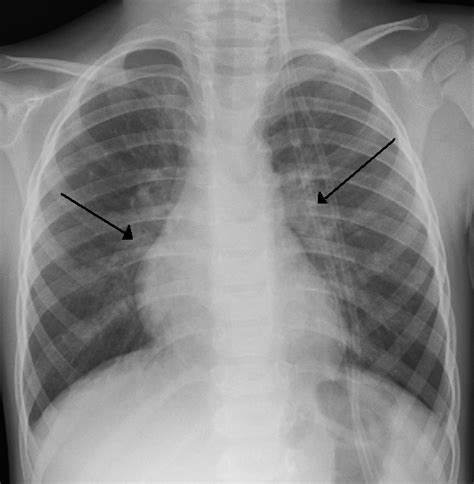

In chronic bronchitis, however, x-rays might show thickened bronchial walls and increased lung markings. These changes reflect long-term inflammation and damage to the airways. Understanding these subtle differences in x-ray findings helps distinguish between acute and chronic bronchitis.

Pneumonia typically shows consolidations or infiltrates on a chest x-ray, indicating areas of lung inflammation filled with fluid or pus. In contrast, a bronchitis x-ray chest in acute bronchitis might appear normal or show subtle changes. This distinction is critical in determining the appropriate course of treatment.